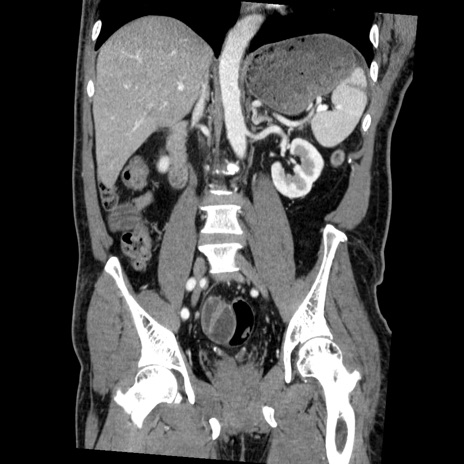

症例22(冠状断像)

【症例】50歳代男性

【主訴】腹痛

【現病歴】AVMからの被殻出血のため回復期リハ病棟入院中。 本日午後3時頃急に下腹部痛が出現した。

【既往歴】AVM、被殻出血、虫垂炎、高血圧

【身体所見】意識晴明、左半身不全麻痺、会話の理解は良好、36.5°C、腹部:膨隆、全体に板状硬、下腹部正中に圧痛点あり、反跳痛-、筋性防御不明、右下腹部にope scar

【データ】WBC 9400、CRP 0.06